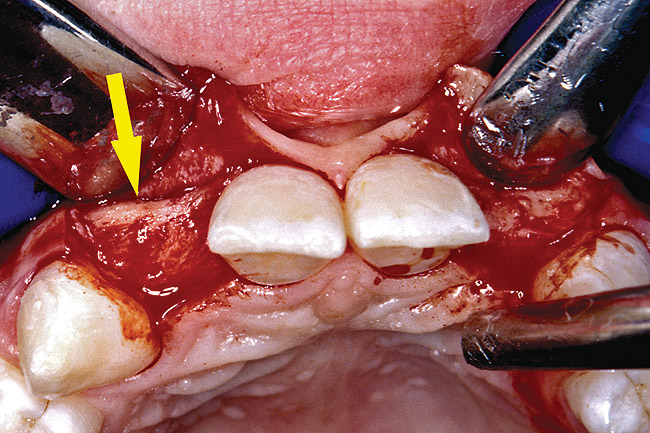

Periapical radiographs were taken to help determine the mesial-distal inclinations of the adjacent tooth roots (Figure 1). The radiographs revealed a serious issue, convergent roots for the right canine and right central, which eliminated that area as a potential implant-receptor site. The space between the left central and canine teeth was minimal, although the roots were relatively parallel. Clinical examination (manual palpation of the root eminences superiorly to the vestibule on the right side) confirmed the root convergence (Figure 2). The flat, wide zone of the keratinized tissue and lack of interdental papilla was evident for the missing right lateral incisor. There was a marked difference in clinical appearance for the left lateral, which could impact the eventual plan of treatment (Figure 3). Other significant clinical findings included bilateral facial bone concavities, which existed as a result of the congenitally missing tooth roots. As a diagnostic cue to the underlying bone topography, it is important to follow the demarcation between attached and unattached gingival tissue, and note the crestal width of the available keratinized tissue (Figure 4).

Figure 2  DIAGNOSTIC INFORMATION Root convergence, buccal view.

Figure 2

Figure 3  DIAGNOSTIC INFORMATION A difference in clinical appearance of the left lateral, buccal view.

Figure 3

Figure 4  DIAGNOSTIC INFORMATION Significant crestal width of keratinized tissue, buccal view.

Figure 4